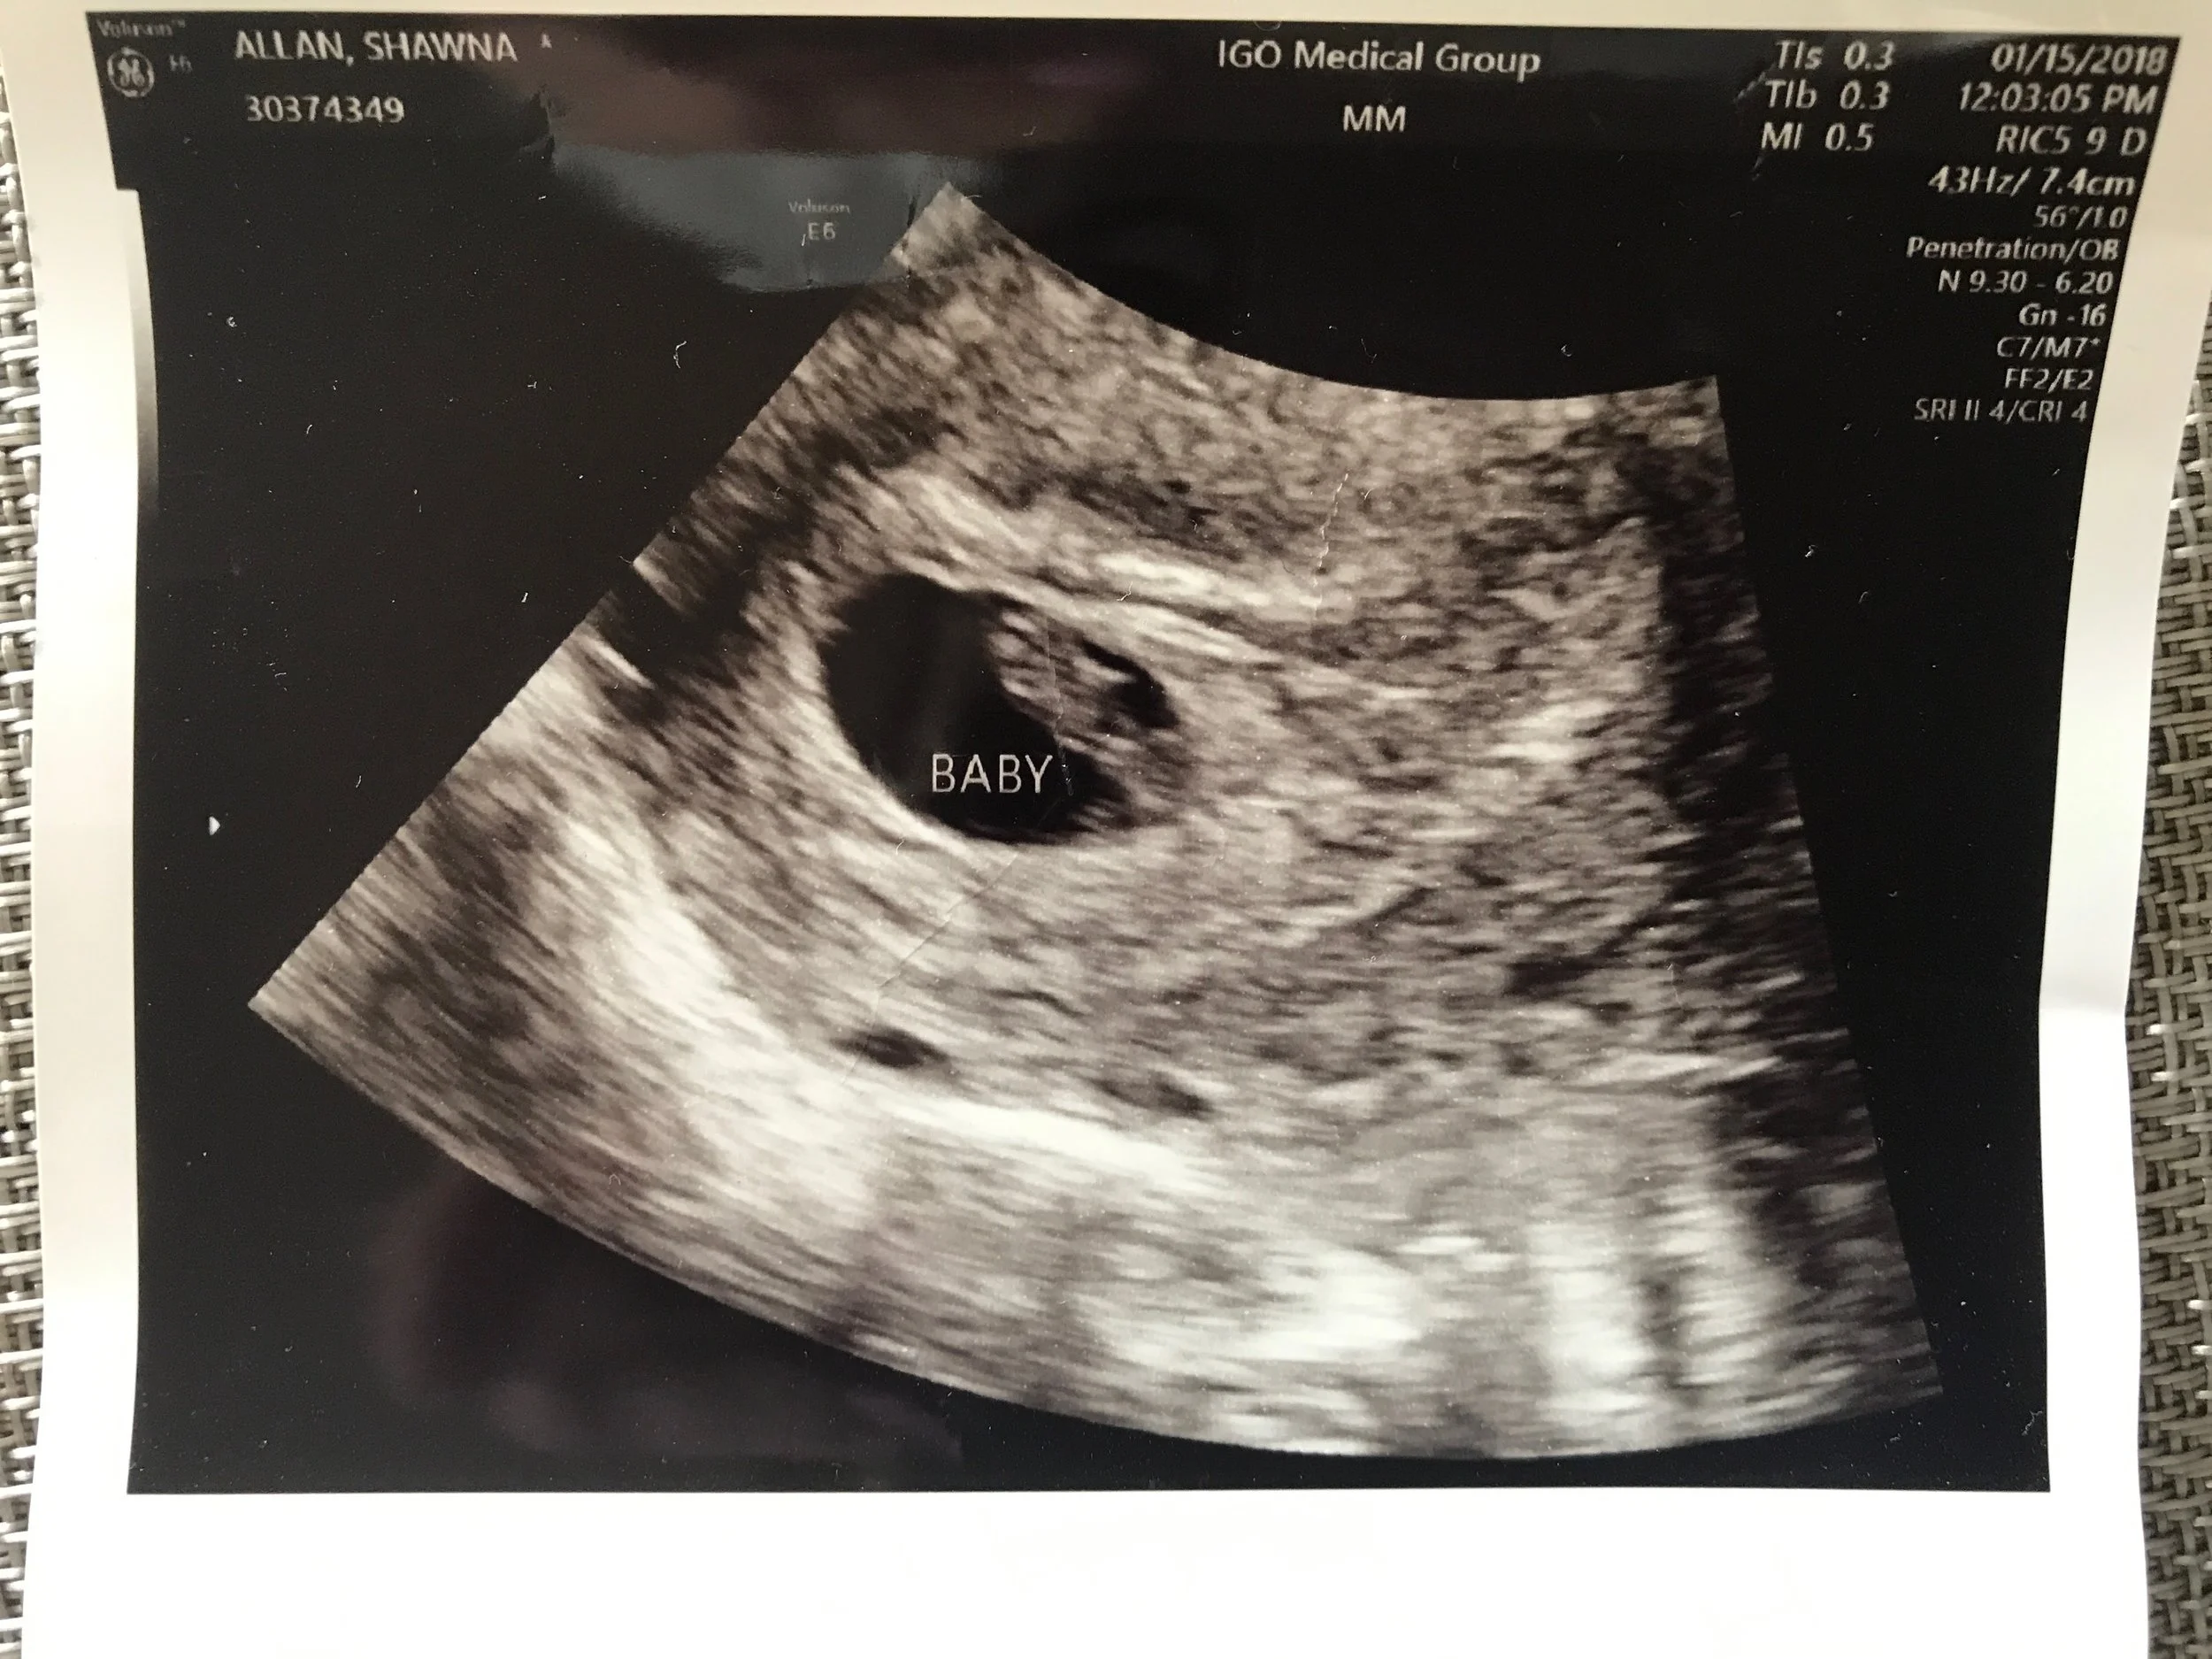

First Ultrasound

We took some time to heal from our experience with IVF. In one regard we were so thankful for it because we wouldn't' have been able to have our son without it. But on the other hand, it had chewed us up and spit us out.We started becoming very comfortable with the idea of our little family of 3. We never intended for Brock to be an only child but maybe it was our path. He was absolutely amazing and we felt so blessed to have him in our lives. It took many months but we were finally at peace with our decision, I was at peace with being "done" and I was proud of us for getting to a good place mentally despite the rollercoaster we had been through.The most ironic thing about this story is that as I'm writing this, I am 4 months pregnant. I didn't do IVF and I don't have a surrogate. After I was told that I would never carry a child again, I stopped tracking my cycles, it was honestly the last thing on my mind. This past December came and went and I knew that I was supposed to get a period but still hadn't. Again, given my history it was the last thing on my mind. It was Thursday night, our family was driving to dinner and the restaurant is close to a Target store so I asked Brett to pull over. I bought a pregnancy test and took it in the Target bathroom (I know, really classy). Shock was an understatement, the test was POSITIVE. I went into my OBGYN office first thing the next morning for a blood test. That afternoon they called me, my HCG results were positive and they asked me to come back in the following Monday for an ultrasound to figure out what was going on and how far along I was. Remember that blank feeling I was talking about earlier? That ultrasound appointment is still a bit of a blur to me. The technician told us "there is the heartbeat" so nonchalantlyand my jaw dropped.I was informed that I was 6 weeks and 4 days pregnant.